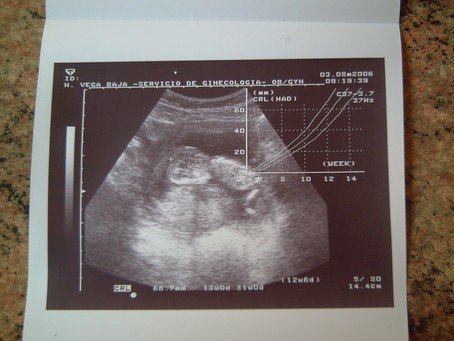

Megjottunk (mar regen csak a nagyfiuval is torodni kellett, most alszik ) borzalmasan boldogan es fulig ero szajjal mert ugy nez ki minden rendben van a picivel, szep, fejlett baba, lattam a dobogo szivecskejet. Nagyokat ugralt, ellokte magat a labaval es ugy ficankolt, meg kifeszitette a testet aztan osszegornyedt, szoval egesz vegig mozgolodott es mi apaval elso latasra beleszerettunk!

Hatalmas "kis"teso 66,7 mm. Pont jo a koranak es ket keze, laba van es szep kis pofija, marmint szerintunk O a leggyonyorubb a vilagon a tesojaval egyutt!

Olyan jo kimondani hogy KISTESO! Nagyon boldog vagyok, azt hiszem latszik, ugye?!

Szerintem jok lettek a kepek de beszkenneltetni meg nem volt idom igy csak lefenykepezve tudom folrakni, azert igy is latszik.

Kép Kép Kép

Remelem meg tudjatok "fejteni" a kepeket! :lol: